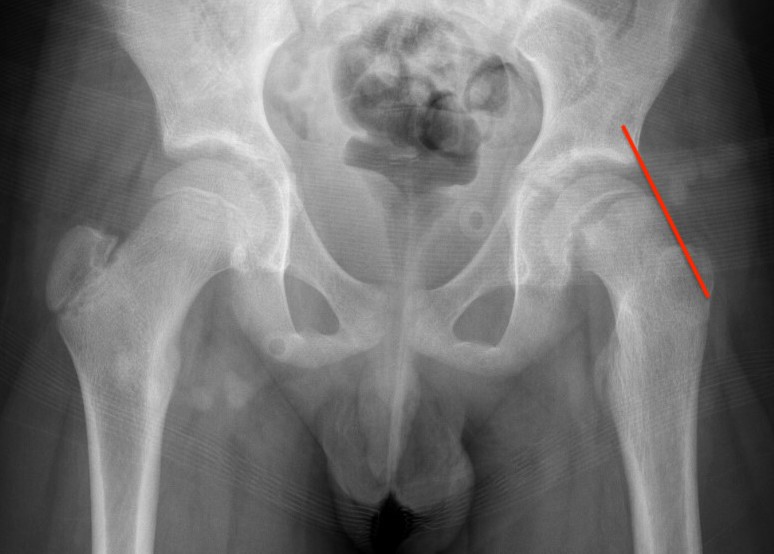

Lateral xray

Mild and moderate SCFE on left hips

Southwick classification

Southwick Angle / Slip Angle

- epiphyseal-diaphyseal angle on frog leg lateral

- mild <30°

- moderate 30- 50°

- severe >50°

Mild Moderate Severe